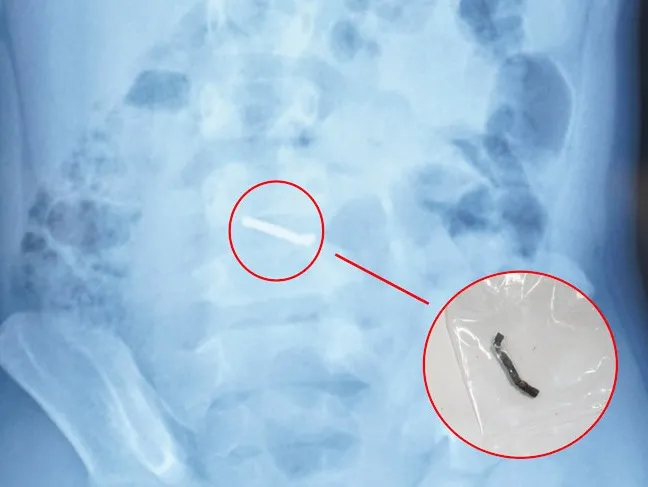

Hình ảnh dị vật qua chụp X-quang và viên nam châm sau khi được các bác sĩ phẫu thuật lấy ra. Ảnh: Bệnh viện Nhi Trung ương

Trong quá trình phẫu thuật, các bác sĩ phát hiện nhiều viên nam châm nhỏ dính vào nhau thành một chuỗi, gây thủng ruột. Các bác sĩ phẫu thuật đã tiến hành lấy dị vật, khâu lỗ thủng và đặt dẫn lưu. Sau 4 ngày, bệnh nhi đã sinh hoạt bình thường, bắt đầu được tập ăn trở lại và dự kiến sẽ được ra viện trong một vài ngày tới.